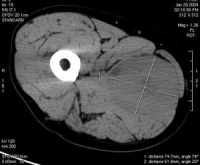

影像学检查:一般无典型的放射学特征,通常无钙化现象。肿瘤可侵蚀并破坏邻近骨质,尤以颅骨前臂、手部和足部多见。应用加造影剂的CT和MRI检查,可较好地显示肿瘤的部位、体积、边缘及其与周围组织的关系。静脉肾盂造影可发现膀胱内不规则充盈缺损肾盂积水等。其它的检查方法包括骨扫描(疑有骨转移)和淋巴管造影(疑有淋巴结转移)。

肿瘤好发于眶上部,尤其鼻上象限眼睑处,也可发生在球后或眶内任何部位,约一半位于哐上方者有上睑表现为急性发病,眶缘部肿块可在短期内迅速增大,很快发展为单侧突眼,结膜水肿,上睑下垂,皮肤充血、肿硬,伴发热,可误诊为眶蜂窝织炎。如肿瘤侵及视神经眼外肌,则视力丧失眼球运动障碍。如不及时治疗,肿瘤可蔓延整个眼眶,累及鼻窦,甚至进入颅内。立即进行CT、MRI和B超等影像检查,能明确肿瘤的部位和范围,CT检查在儿童如显示眶骨破坏则有助于确诊。如临床诊断不明确,可作活检病理诊断。此外,应体检耳前、颈淋巴结有否局部转移。